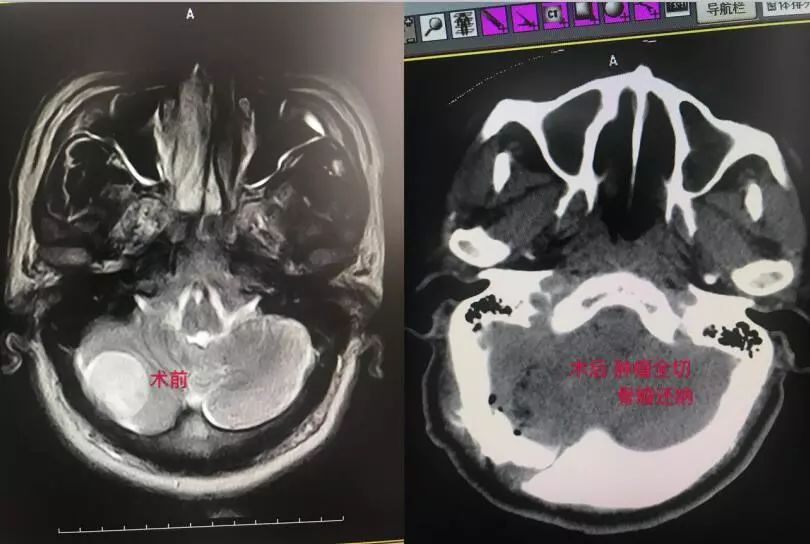

5、后颅窝病损切除、骨窗一期修复:

经过我们的不断努力和学习,在做好原有成熟手术的基础上,对复杂高难手术方面也取得了一些进展,比如桥小脑角区占位、镰旁巨型脑膜瘤、动脉瘤的夹闭、脑干出血的手术、胶质瘤手术等: